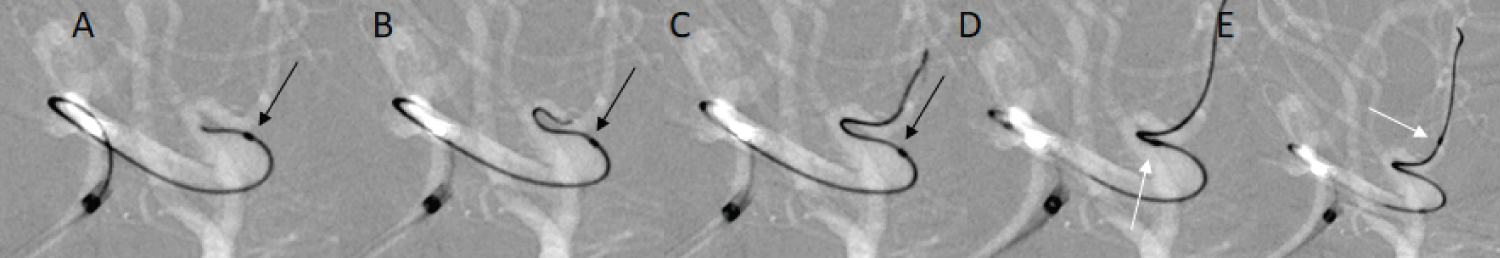

In ten cases, an intra-aneurysmal insertion technique was not necessary; in the seven cases in which this technique was used, only a minor catheter kickback phenomenon was observed during microwire (CHIKAI 315 cm EXC) navigation, and the stress on the aneurysmal wall may be reduced (Figure 1). The stiffness of the tip of the Echelon 10 MicroCatheter seemed to facilitate insertion. In two large aneurysms (> 10 mm), the flexure was released safely after intra-aneurysmal insertion of the microcatheter (Figure 2). Furthermore, in three cases of ruptured aneurysm, SDC guidance was performed without any stress on the aneurysmal wall (Figure 3). In two cases, our attempt to insert the Excelsior XT-17 Microcatheter failed. We then inserted the Echelon 10 MicroCatheter successfully (Figure 4). No thromboembolic events, no vessel injury, and no perforation of the aneurysm occurred during the exchange procedures with the Asahi CHIKAI 315 cm EXC.

Figure 1: A case of unruptured aneurysm in the right middle cerebral artery. The microwire navigation from the Echelon 10 MicroCatheter in the aneurysm is shown. Minimum kick back of the tip (Black arrows; A, B, and C) is shown, and tracking was smooth, with lower pressure on the aneurysmal wall (White arrows; D and E). View Figure 1

Intra-aneurysmal navigation is frequently mandatory in the treatment of large and giant aneurysms. In particular, releasing the flexure of the catheter system in giant aneurysms is not easy. Oran, et al. demonstrated the "rapid pull back technique" [14] and Sakamoto, et al. reported the "stent anchor technique" [15] as methods to use when releasing the flexure; these are effective options, but in both techniques, the whole catheter system may exit the distal artery, and recovering the catheter in such a situation is laborious. In our study, it was not easy to release the flexure in the two aneurysms that measured more than 15 mm in diameter, but pulling the intermediate catheter and the Echelon 10 MicroCatheter together resulted in successful release (Figure 2). The Echelon 10 MicroCatheter seemed to be effective for such situations, and this technique was thus considered a useful option. Guidance of the microwire to the target vessel with lower pressure against the aneurysmal wall was possible during intra-aneurysmal navigation (Figure 1).